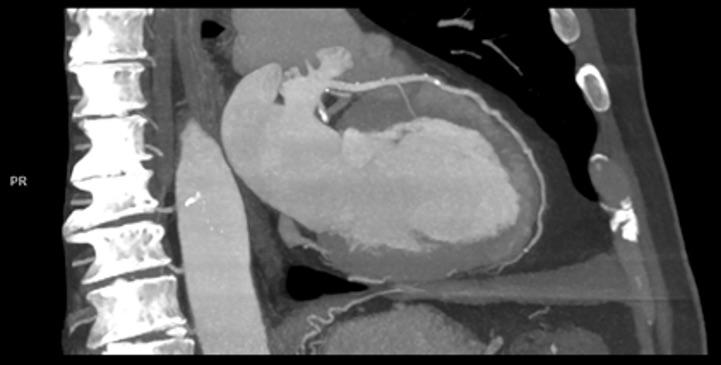

Per the guideline, unless obstructive CAD can be excluded based on clinical evaluation alone, either non-invasive functional imaging or anatomical imaging using coronary CTA should be used as the initial test to rule out or establish the diagnosis of CCS.

The new guideline suggests that "Coronary CTA is the preferred test in patients with a lower range of clinical likelihood of CAD, no previous diagnosis of CAD and characteristics associated with a high likelihood of good image quality."

“Depending on patient characteristics, local expertise and availability, as well as patient-specific considerations, physicians should decide between coronary CTA and ischemia testing,” said ESC President-elect Stephan Achenbach, M.D., FSCCT. “This is a recognition of the numerous trials that have been performed to establish the usefulness and reliability of CT angiography as a first-line examination."